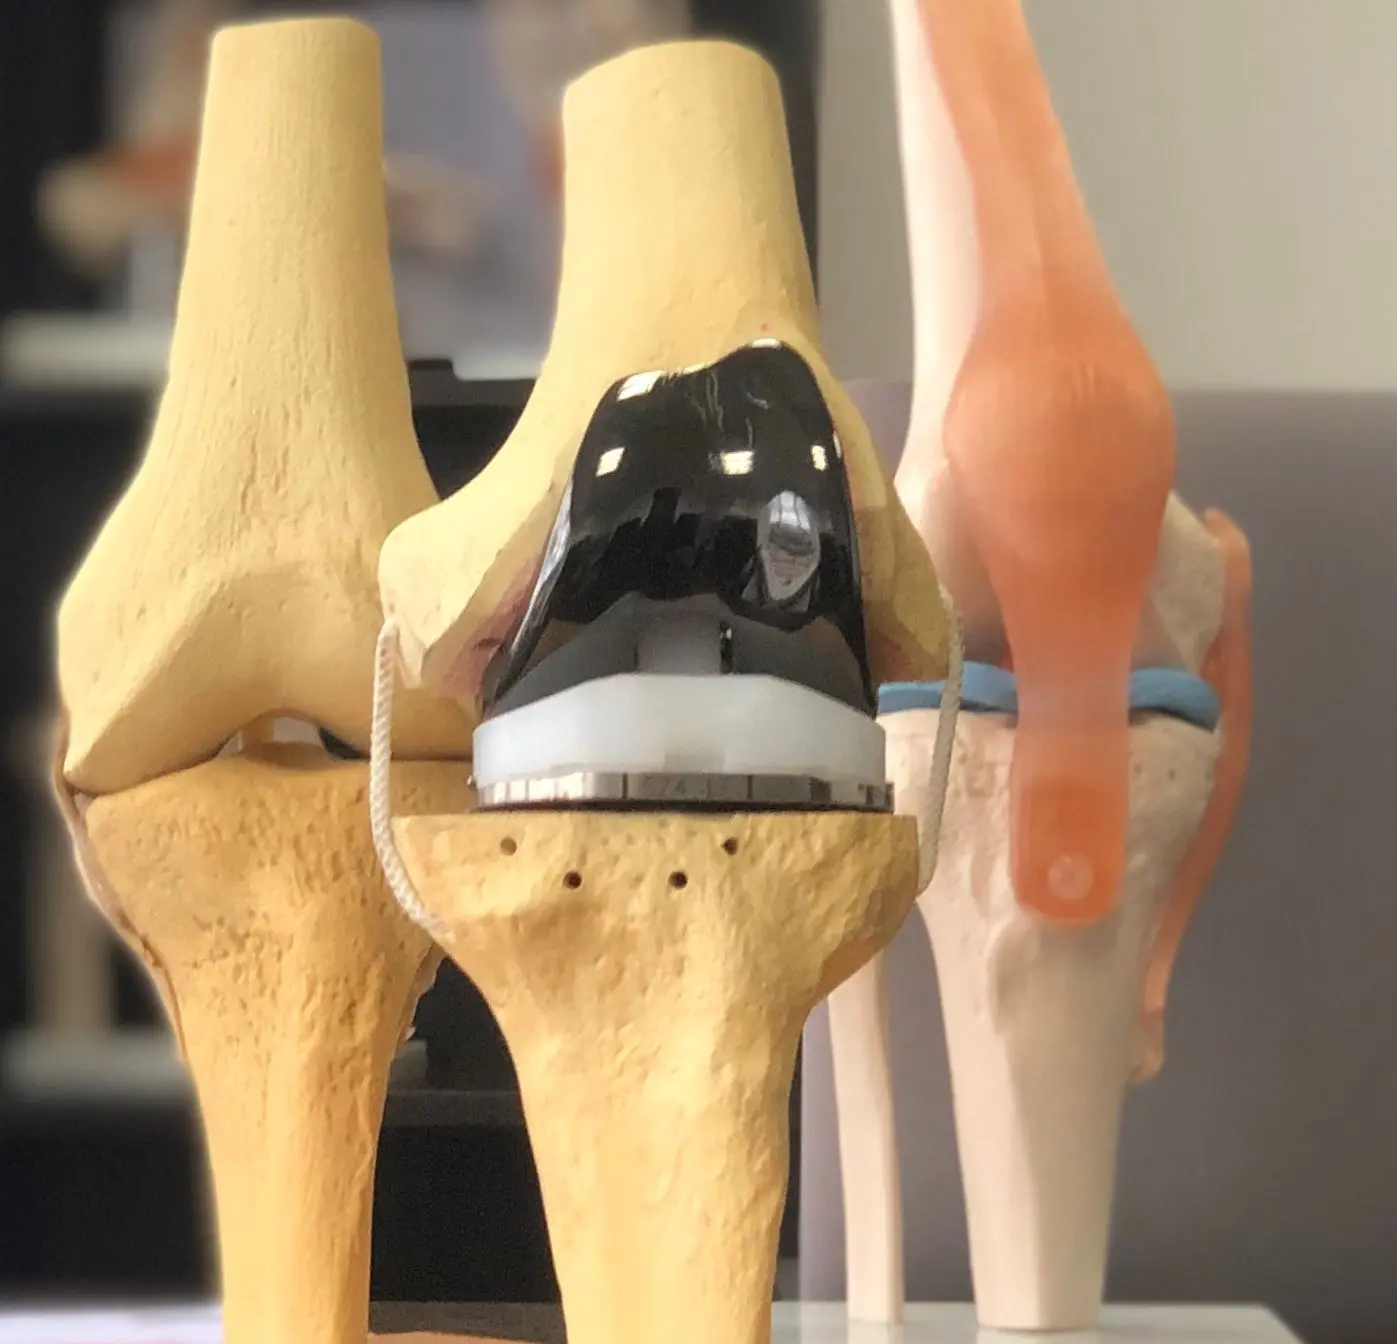

Cirugía robótica y prótesis

Cirugía Robótica de Rodilla en Quito: tu implante con precisión milimétrica.

Menos dolor, recuperación acelerada y mayor durabilidad de tu prótesis. Tecnología de vanguardia guiada por mi experiencia en cirugía de rodilla, incluyendo navegación quirúrgica cuando el robot no está disponible. Parte de la ruta de trastornos degenerativos y artrosis.

Galería de fotos